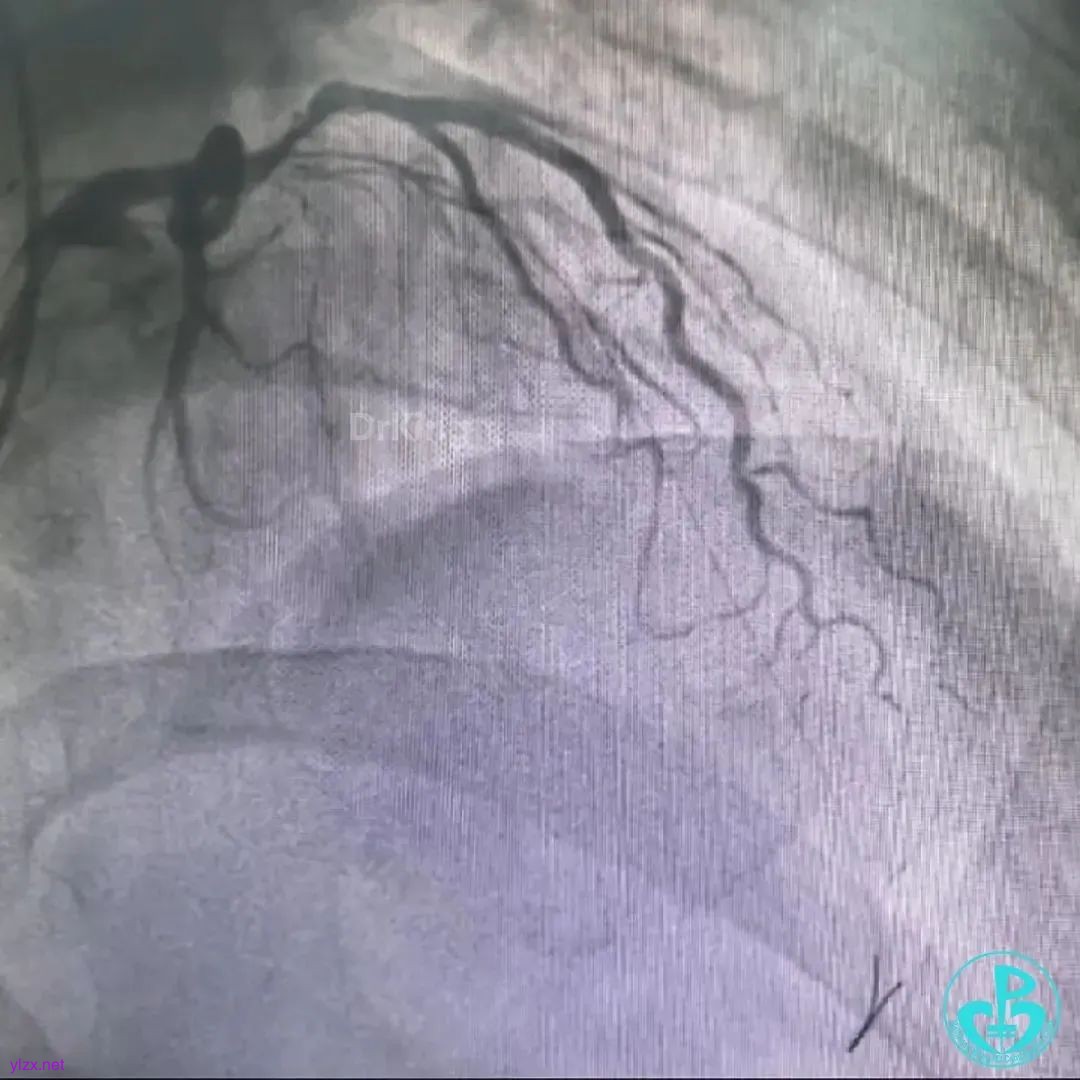

“螺旋”棘突球囊2atm拉栓后造影TIMI血流2级,后植入2枚支架,造影显示TIMI血流3级。

遗憾的是远端末梢还有少量血栓。